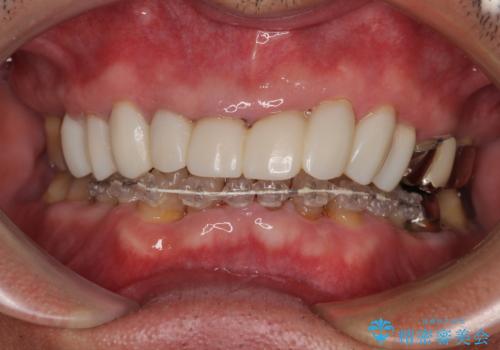

上下ともに前歯のセラミッククラウンによる補綴治療を希望されていましたが、下顎前歯は叢生が強いため、補綴治療前に部分矯正を行って歯列を整えた上で、補綴治療を行うこととしました。

臼歯部には歯周ポケットのある箇所が散見されましたが、まずは前歯を治療したいとのことで、治療を進めました。

ディープバイトにより臼歯部に負担のかかる咬合であったので、補綴治療後には、矯正治療の後戻り防止もかねて、睡眠時にマウスピースを装着するように指示しました。